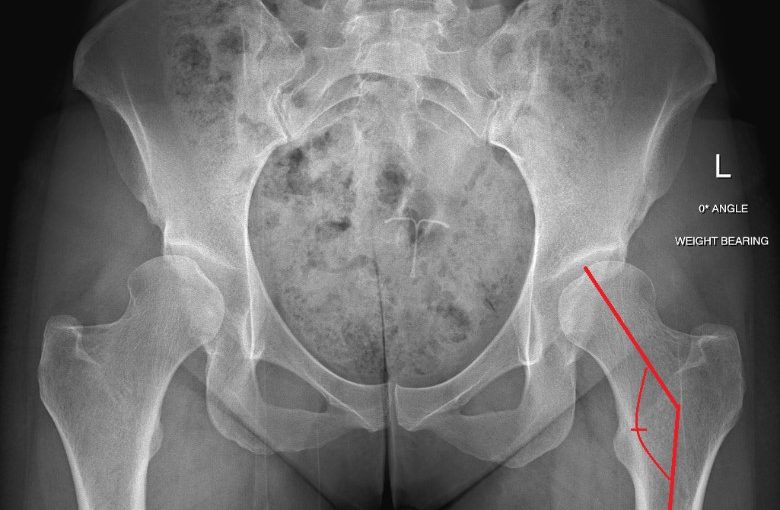

Do you want to deepen your understanding of your hip condition? Check out this resource that dives into the measurements on your radiology report and what they mean. Hip Dysplasia: What’s With All Those Angles?